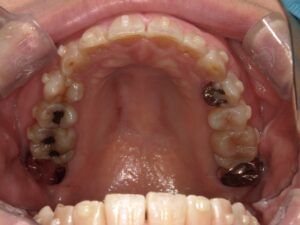

上顎の歯並びの変化

綺麗な連続性のあるアーチになってきました。